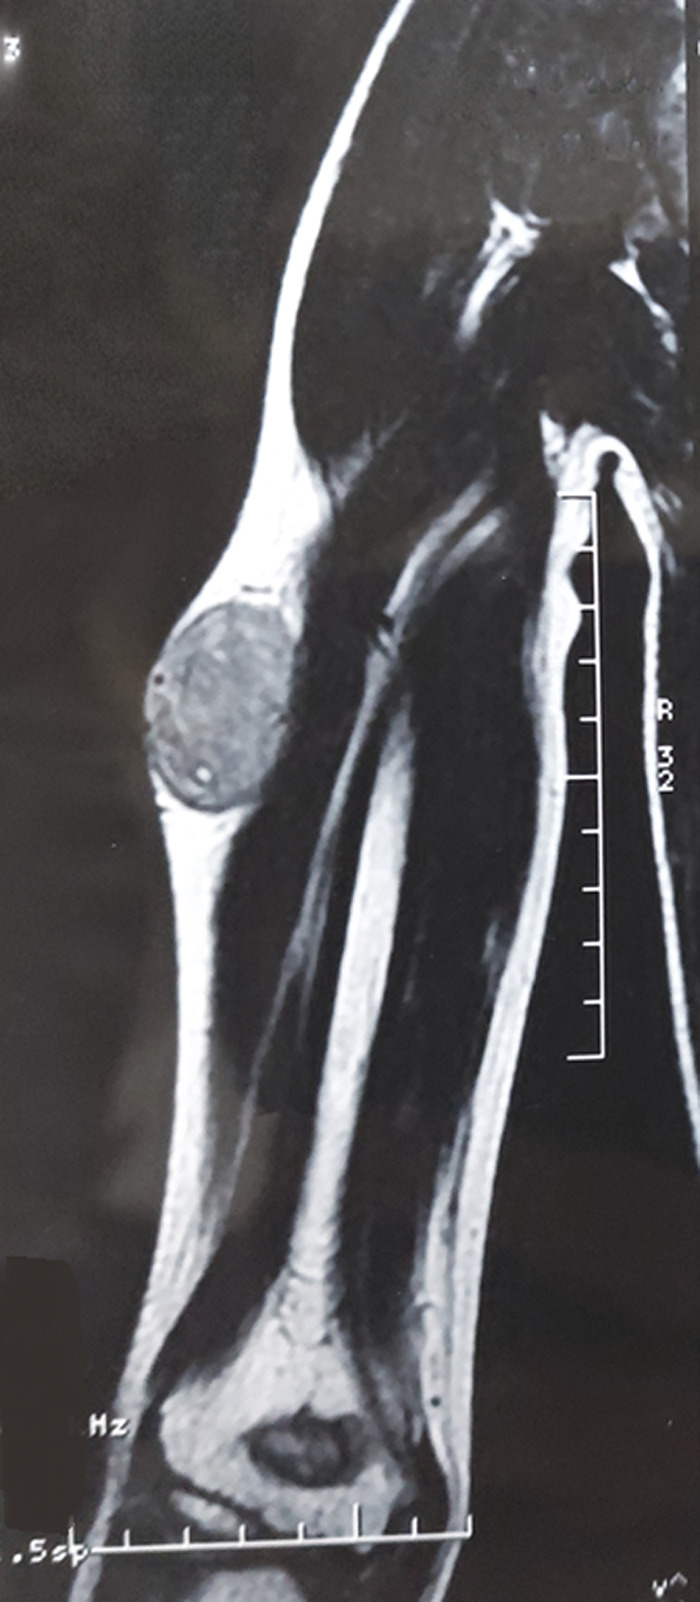

Ewing家族软组织肿瘤(EFT)代表了一种不确定组织发生的肿瘤谱,发生在没有骨累及的软组织中。它们包括骨骼外尤文氏肉瘤和原始神经外胚层肿瘤。这些肿瘤在形态上与骨骼系统的尤文氏肉瘤难以区分。已知易位相关肿瘤,它们具有共同的非随机易位,导致EWSR1基因在22q12区域与ETS家族转录因子中的一个成员融合。EFT主要发生在青少年和30岁以下的年轻男性中,几乎可以出现在任何地方,但最常见于四肢的深层软组织。本研究报告一例罕见的发生在14岁男孩上臂的EFT病例,他表现为右臂肿块疼痛发展了6个月,同时强调了这种罕见疾病的主要组织学,免疫组织化学和分子特征,以及相关诊断方法的原始流程图,用于鉴别诊断。

The Ewing family tumors (EFT) of soft tissue represent a spectrum of neoplasms of uncertain histogenesis, arising in soft tissue without bone involvement. They include Extraskeletal Ewing Sarcoma and Primitive Neuroectodermal Tumor. These tumors are morphologically indistinguishable from Ewing sarcoma of the skeletal system. Known to be translocation-associated neoplasms, they share a common non-random translocation leading to the fusion of the EWSR1 gene on the 22q12 region, with one of the many members of the ETS family of transcription factors. Occurring mainly in adolescents and young men under the age of 30, EFT´s may arise virtually anywhere, but are most common in deep soft tissues of the extremities. The purpose of this work is to report a rare case of an EFT arising in the upper arm of a 14-year-old boy, who presented with a painful right arm mass evolving for 6 months, while highlighting the main histological, immunohistochemical and molecular features of this rare condition, along with an original flow chart of a relevant diagnostic approach for differential diagnosis.